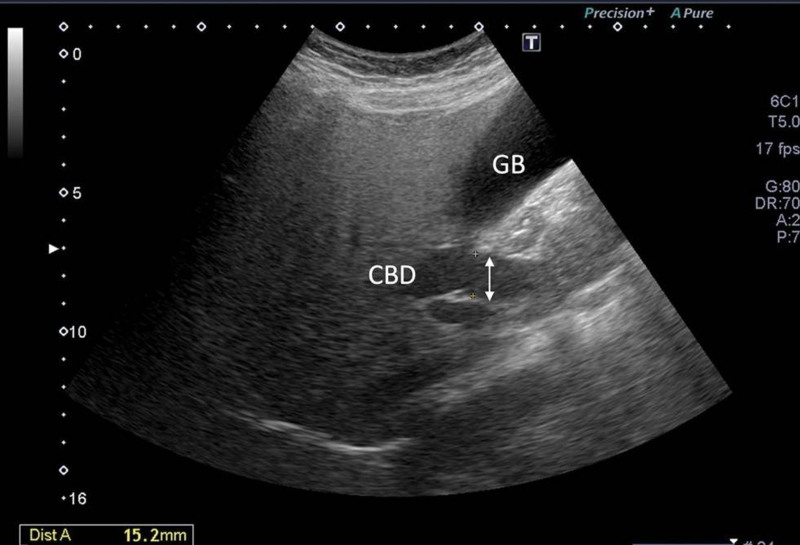

A 54-year-old woman with a medical history of hypertension and hyperlipidemia presented to the outpatient department complaining of persistent epigastric dull pain. Abdominal ultrasonography revealed significant dilation of the CBD (up to 15.2 mm); however, no obvious intraductal mass, bile duct wall thickening, CBD stones, or pancreatic head tumors were identified (Fig. 1). Subsequent abdominal CT demonstrated a contrast-enhanced tumor-like mass measuring approximately 1.6 cm in the distal CBD, characterized by wall thickening without distinct intraductal lesions. Magnetic resonance imaging (MRI) confirmed narrowing of the distal CBD with mild upstream dilatation measuring 10.9 mm, without liver, pancreatic, or lymph node involvement (Fig. 2). Physical examination of the abdomen revealed no tenderness, and the patient denied experiencing fever, nausea, vomiting, or loss of appetite. Laboratory investigations revealed an elevated level of γ-glutamyl transferase (GGT) at 130 U/L, while regular blood tests, as well as levels of carcinoembryonic antigen (CEA), cancer antigen 153 (CA153), and CA199, were within normal ranges (Table 1). Suspecting a bile duct tumor, a Whipple procedure was performed for both diagnostic and definitive treatment purposes (Fig. 3). Histological examination of CBD sections revealed adenomyomatous hyperplasia characterized by clusters of benign biliary glands embedded within fibromuscular stroma and surrounded by lymphoplasmacytic inflammatory cells (Fig. 4). The lesion exhibited no signs of malignancy, confirming its benign nature. The patient experienced a satisfactory recovery and was discharged 19 days post-surgery.